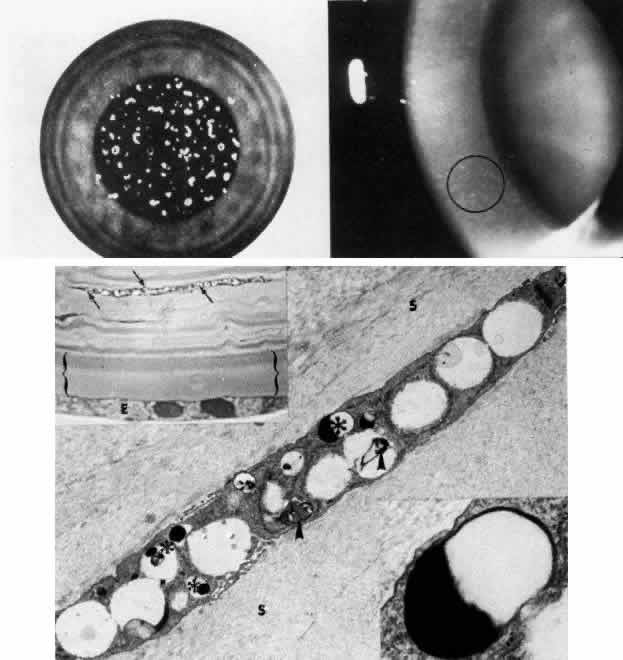

Fig. 3. Peters' anomaly. Schematic drawing of ocular features. Top left. Clinical photo of typical bilateral Peters' anomaly with large, dense central leukomata, which was successfully treated by penetrating keratoplasty with optical iridectomy of the fellow eye. Top center. Intraoperative photo demonstrates adhesion of the lens to the posterior cornea as a corneal button (grasped with forceps) is trephined. Top right. Successful penetrating keratoplasty of a patient with bilateral Peters' anomaly. Bottom, upper left. Survey light photomicrograph of a corneal button from the case illustrated clinically (top center) shows termination of Bowman's membrane (at arrowhead) corresponding to the area of adhesion between the posterior cornea and lens (L). Descemet's membrane, present peripherally, terminates centrally in a layer of retrocorneal fibrous tissue (*) interposed between the lens and stroma. Direct contact between the retrocorneal fibrous tissue and continuous lens capsule is evident (paraphenylenediamine, phase contrast, × 60). Bottom, lower left. Phase-contrast micrograph of posterior cornea adjacent to a central stromal defect shows termination (at arrowhead) of undulating Descemet's membrane between the stroma and retrocorneal fibrous tissue (paraphenylenediamine, × 400). Bottom right. Transmission electron micrograph of posterior cornea shows attenuated keratocytes (K) with phagocytic contents, disorganized posterior stromal lamellae, and markedly thin and multilaminar Descemet's membrane (DM) with attenuated but continuous endothelium (E). AC, anterior chamber. (x 7000) (Schematic. Grayson M: Diseases of the Cornea, p 29. St. Louis, CV Mosby, 1979)

Histopathologic changes are present in all layers of the cornea in Peters' anomaly.19,20,38–41 Often the anterior changes, which include disorganization of epithelium, fibrovascular pannus, and loss of Bowman's layer due to long-standing edema, are secondary to the posterior abnormalities. Fluid lakes are also present in the affected stroma.

In the peripheral and unaffected areas, the corneal endothelium forms a continuous monolayer, and Descemet's membrane is of normal, uniform thickness (approximately 5μm). In the area of defect, however, endothelium and Descemet's membrane can terminate abruptly or be severely attenuated. The affected Descemet's membrane is composed of multiple laminations of basement membrane-like material, with interspersed collagen fibrils and fine filaments. Since such abnormal material is elaborated by the corneal endothelium, a fibroblastic metaplasia of the endotheliogenic mesenchyme is likely, as is thought to occur in a number of corneal conditions in which the endothelium is similarly disturbed to secrete a posterior collagen layer.42,43

The lens abnormalities in Peters' anomaly are characterized histologically by a stalklike connection between the lens and the posterior corneal defect, suggesting primary incomplete separation of the lens vesicle. Alternatively, there may be contact of a morphologically intact lens to the posterior cornea, suggesting subsequent anterior displacement of a normally developed lens.

There are several reasonable explanations for a central corneal leukoma of the Peters' variety. One is incomplete central migration of corneogenic mesenchyme (i.e., neural crest cells), accounting for posterior endothelial and stromal defects.23 This is corroborated by the finding of abnormally large stromal collagen fibrils of 36 to 60 nm in some patients with Peters' anomaly. A similar abnormality of mesenchymal development is found also in sclerocornea and congenital hereditary endothelial dystrophy.22 Another explanation of posterior corneal leukoma of a Peters' type is an in utero subluxation of the lens, either prior to or after its full development, in either case interrupting the normal migration or function of the developing endothelium.